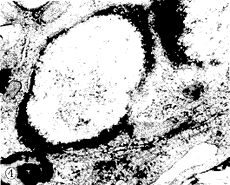

2.2 骨髓造血细胞的形态学改变:瑞氏姬姆萨染色的骨髓涂片显示,射线损伤后造血细胞的形态学改变,主要有细胞空泡变,染色质浓缩,细胞核畸型化。细胞核呈着色较深的团块状固缩、碎裂,形成膜结构包围部分细胞核和细胞质的细胞碎片,即凋亡小体(图1)。电镜下除了可见光镜的改变外,还可见损伤细胞的细胞膜或突起减少或起皱、发泡样改变,胞浆中有大小不等的空泡。细胞质内可见髓鞘样变性,线粒体和内质网的结构尚好(图2)。核仁边移,染色质浓缩成团块样(图3),或边缘化,形成环状或新月体样结构(图4)。晚期可见细胞核碎裂,碎裂的细胞核有较完整的核膜结构包裹(图5)。凋亡小体可被其他细胞吞噬。

图2 凋亡早期细胞膜发泡样改变,细胞质广泛空泡形成和髓鞘样变性TEM×8,000